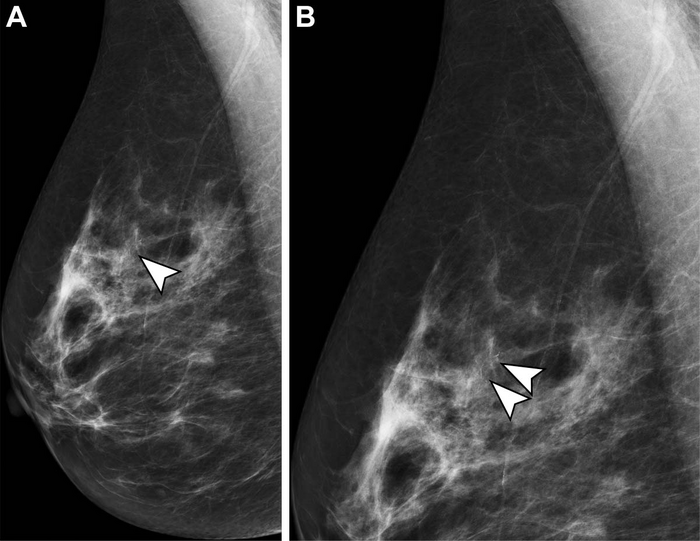

OAK BROOK, Ill. – When double reading screening mammograms, radiographers (technologists) trained for the task perform as well as radiologists in key areas, according to a study published in Radiology , a journal of the Radiological Society of North America ( RSNA ).

Double reading, the process of interpreting a radiological image with two or more sets of eyes, is the standard of care throughout Europe and it has been shown to improve cancer detection rates while simultaneously keeping recall rates low. The National Health Service Breast Screening Program (NHSBSP) in the United Kingdom (U.K.) has over 80 screening centers in England, where over 2 million women are screened annually.

To mitigate the strains put on the healthcare system due to increased workload and radiologist shortages, the NHSBSP has been utilizing non-radiologists as part of double reading since the 1990s. While the traditional role of radiographers is to perform the mammogram, the NHSBSP recruits radiographers who undergo extensive additional postgraduate training to interpret the mammograms. They also participate in the same quality assurance standards as radiologists.